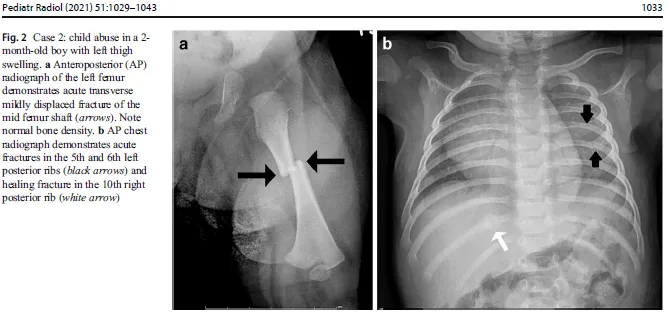

- Metaphyseal Corner Fractures (MCF) / Bucket Handle Fractures (Classical Metaphyseal Lesions - CML).

- Posterior Rib Fractures (due to squeezing/shaking).

- Multiple fractures in various stages of healing.

- Any fracture in a non-ambulatory infant (e.g., femur, humerus <1 year old).

⭐ Metaphyseal corner fractures (CML) are virtually pathognomonic of non-accidental injury (NAI).